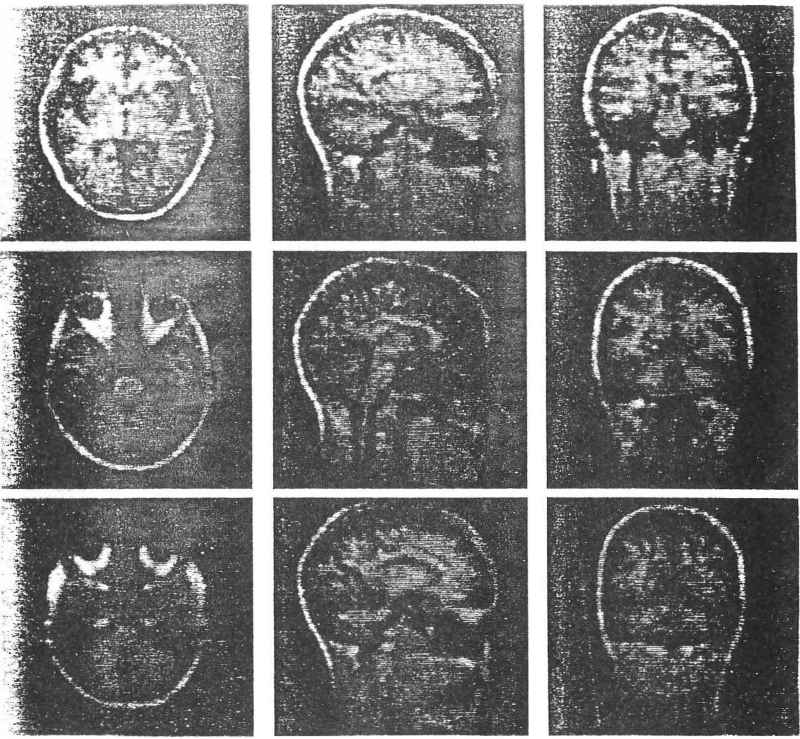

Sur la figure 17 on a reconstitué neuf images d’une tête humaine à partir d’une matrice de données tridimensionnelles portant sur la distribution des protons des molécules de lipides et d’eau dans le sang et les tissus.

Fig. 17. Les 3 coupes transverses de la gauche sont faites à des niveaux de profondeurs différentes :

à l’intérieur du cerveau (en haut), au niveau de l’œil (au milieu) et juste au-dessous de l’œil (en bas).

Les 3 images centrales sont des coupes longitudinales passant par le plan central (au centre) et par deux plans parallèles à trois centimètres de part et d’autre du plan central. Les 3 images de droite présentent la tête vue de face au point le plus large du cerveau (en haut) et à 2 endroits situés plus en arrière.